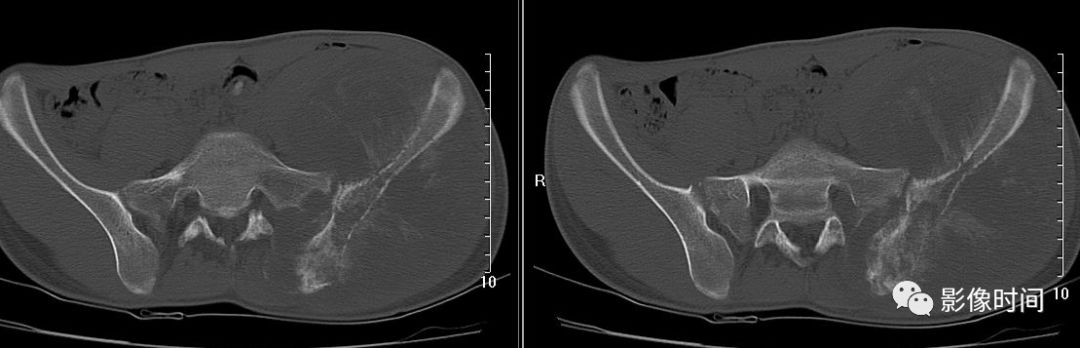

四、肿瘤内液-液平面

肿瘤内液-液平面多数是病灶内囊变出血所致,MRI T2W1 为上部呈高信号下部呈中低信号的液-液平面。CT 可为上部低密度下部高密度的液-液平面(图 32)。液-液平面常见于动脉瘤样骨囊肿、但也可见于骨内腱鞘囊肿(图 33)、囊性血管瘤病等其他肿瘤和肿瘤样病变。

图 32 肿瘤内液-液平面:动脉瘤样骨囊肿

图 33  肿瘤内液-液平面:动脉瘤样骨囊肿